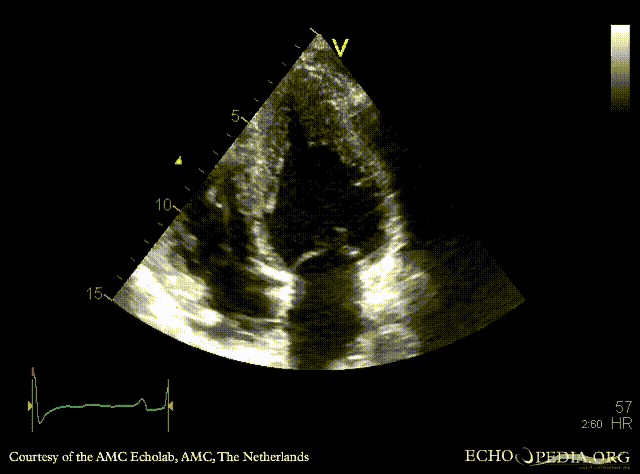

In primary mitral regurgitation, either of these two ECHO findings warrant mitral valve surgery regardless of symptoms.

What is an LVEF ≤60% or End Systolic Dimension ≥40 mm?